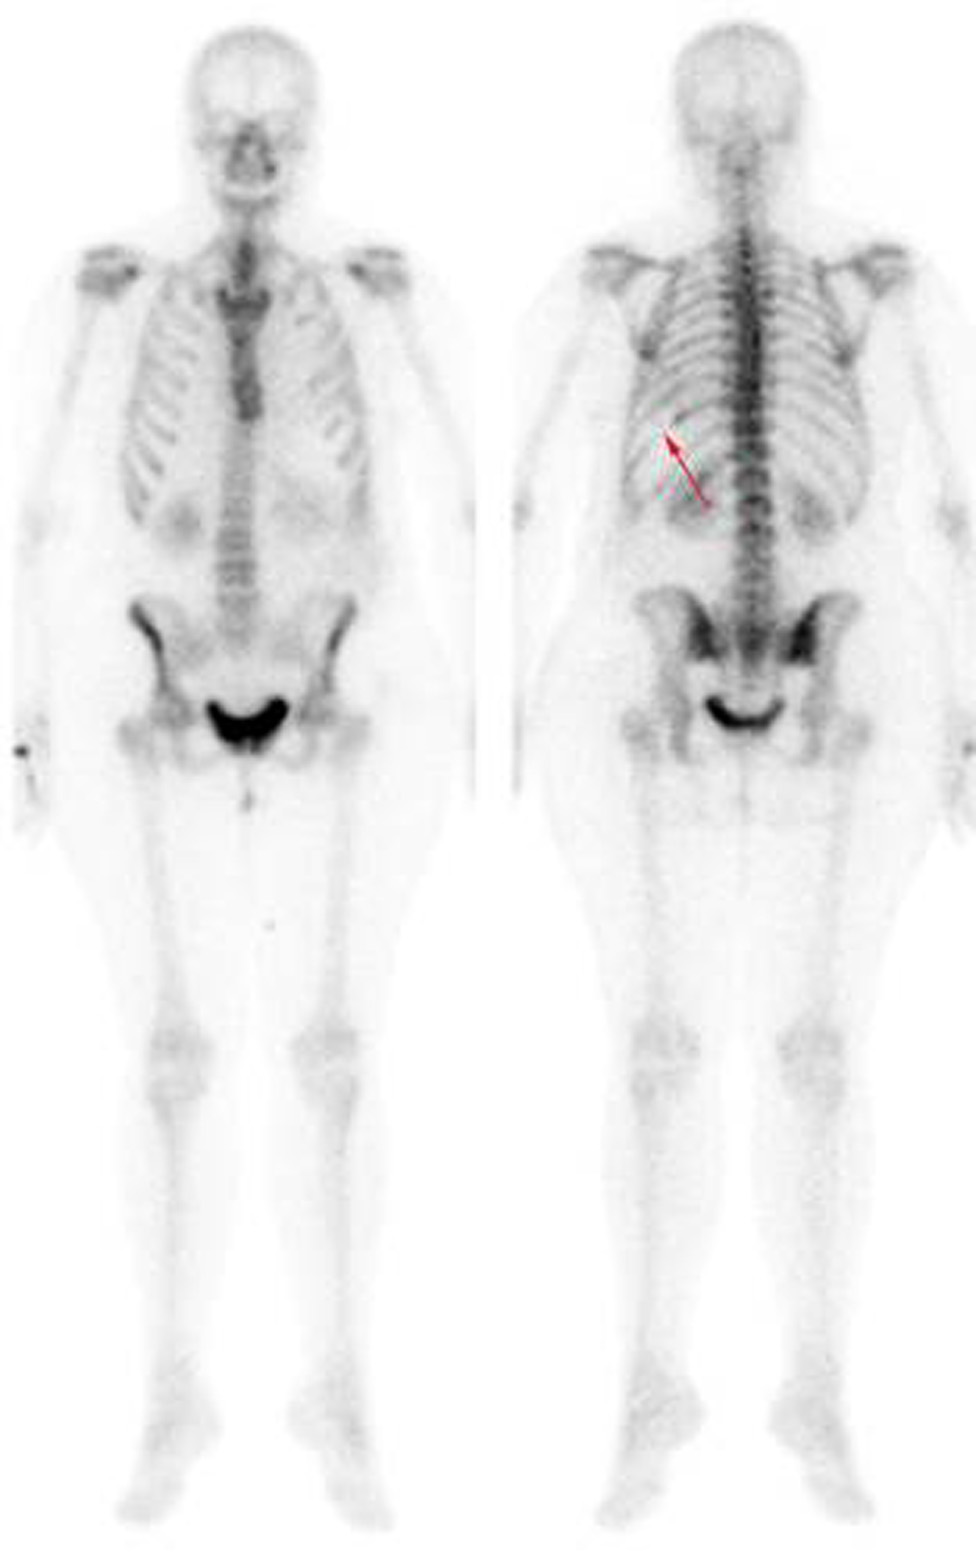

Thoracentesis was performed for evacuation with output of serosanguineous fluid with the following analytical data: glucose 97 mg/dl, LDH 179 UI/l, erythrocytes 571100/ μL, leukocytes 11620/ μL (3% polymorphonuclear, 97% mononuclear), proteins 5.3 g/dl, pH 7.43, rheumatoid factor 9.1 UI/ml, amylase 27 UI/l, cholesterol 86 mg/dl, triglycerides 26 mg/dl, adenosine deaminase (ADA) 13 UI/l. Negative flow cytometry of the pleural fluid for lymphoid infiltration. Cytology of the fluid without cellular atypias. Cultures of the pleural fluid for bacteria, mycobacteria, parasites and fungi were negative. Also, the Mantoux test and the gamma interferon test with quantiferon-TB(r) were negative for latent tuberculosis infection. The serology tests for hepatotropic viruses and human immunodeficiency virus (HIV) were negative. The mammography and the gynecologic ultrasound were normal. Both the bone scintigraphy (Fig. 2) and the CT scan (Fig 3), thoracic MRI and PET revealed hypoplasia and an osteolytic lesion in the 10th and 6th left rib arches together with effusion, significant left pleural inflammation and involvement of adjacent soft parts.

Figure 3. Positron emission tomography. A. shown the absence of the 6th and B. 10th left ribs arches.